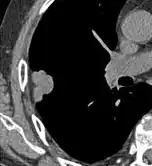

Histopathology

For cases suspicious enough to proceed to biopsy, small biopsies can be obtained by fine needle aspiration or bronchoscopy are commonly used for diagnosis of lung nodules.[19] CT guided percutaneous transthoracic needle biopsies have also proven to be very helpful in the diagnosis of SPN.[6]

In selected cases, nodules can also be sampled through the airways using bronchoscopy or through the chest wall using fine-needle aspiration (which can be done under CT guidance). Needle aspiration can only retrieve groups of cells for cytology and not a tissue cylinder or biopsy, precluding evaluation of the tissue architecture. Theoretically, this makes the diagnosis of benign conditions more difficult, although rates higher than 90% have been reported.[20] Complications of the latter technique include hemorrhage into the lung and air leak in the pleural space between the lung and the chest wall (pneumothorax). However, not all these cases of pneumothorax need treatment with a chest tube.[21]